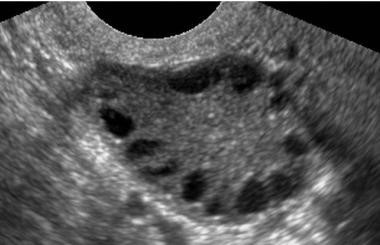

Polycystic Ovary Syndrome (PCOS) a hormonal disorder that affects reproductive aged women. It is one of the most common causes of infertility and is estimated that 70-80% of women with PCOS have infertility. The name PCOS is misleading as these patients do not have large cysts on their ovaries, instead there are an increased number of visible follicles (small fluid filled sacs that hold the eggs) on the ovaries.

- Polycystic appearing ovaries on ultrasound- having more follicles on the ovaries than the average person. This is seen by performing a pelvic ultrasound and visualizing the ovaries. Patients may often have a classic “string of pearls” appearance of the ovaries (as seen above).